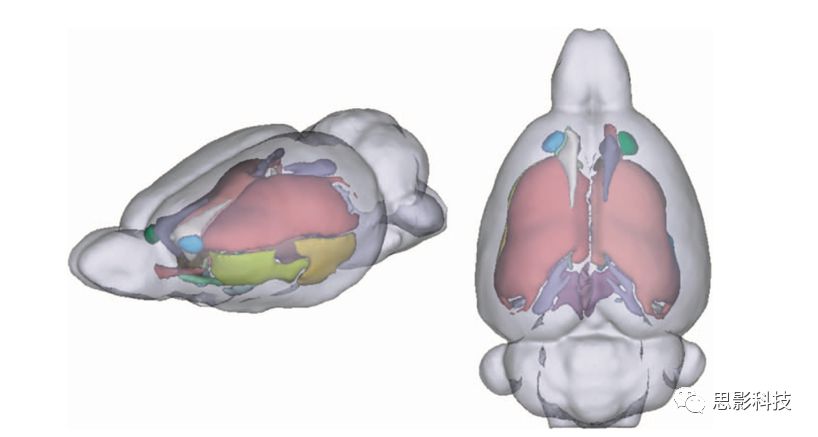

三、sMRI數(shù)據(jù)處理業(yè)務(wù)

1、基于體素的形態(tài)學(xué)分析(VBM

借助FSL/VBM8等工具包對(duì)T1像進(jìn)行分割、配準(zhǔn)并計(jì)算灰白質(zhì)體積密度。

灰白質(zhì)分析圖例